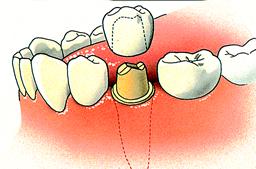

Een tandheelkundige kroon

Wanneer u een verzwakte, beschadigde, verkleurde of gebroken tand of kies heeft, kan een kroon een mooie oplossing voor u zijn.

Een kroon is een vaste vervanging van het zichtbare gedeelte van een tand of kies. De porseleinen kroon heeft de kleur en vorm van een natuurlijke tand. Wanneer u een tand of kies mist of als zowel uw tand als tandwortel zijn beschadigd, is er de mogelijkheid eerst een implantaat te plaatsen waarop de kroon kan worden bevestigd.

- Eerste stap: nadat de beschadigde tand of kies -onder plaatselijke verdoving- door onze tandarts iets is bijgeslepen, wordt er een afdruk van de tand gemaakt. Op basis hiervan maakt een tandtechnisch laboratorium een passende kroon.

- Tweede stap: de kroon wordt als een kapje over uw beschadigde tand of kies geplaatst.